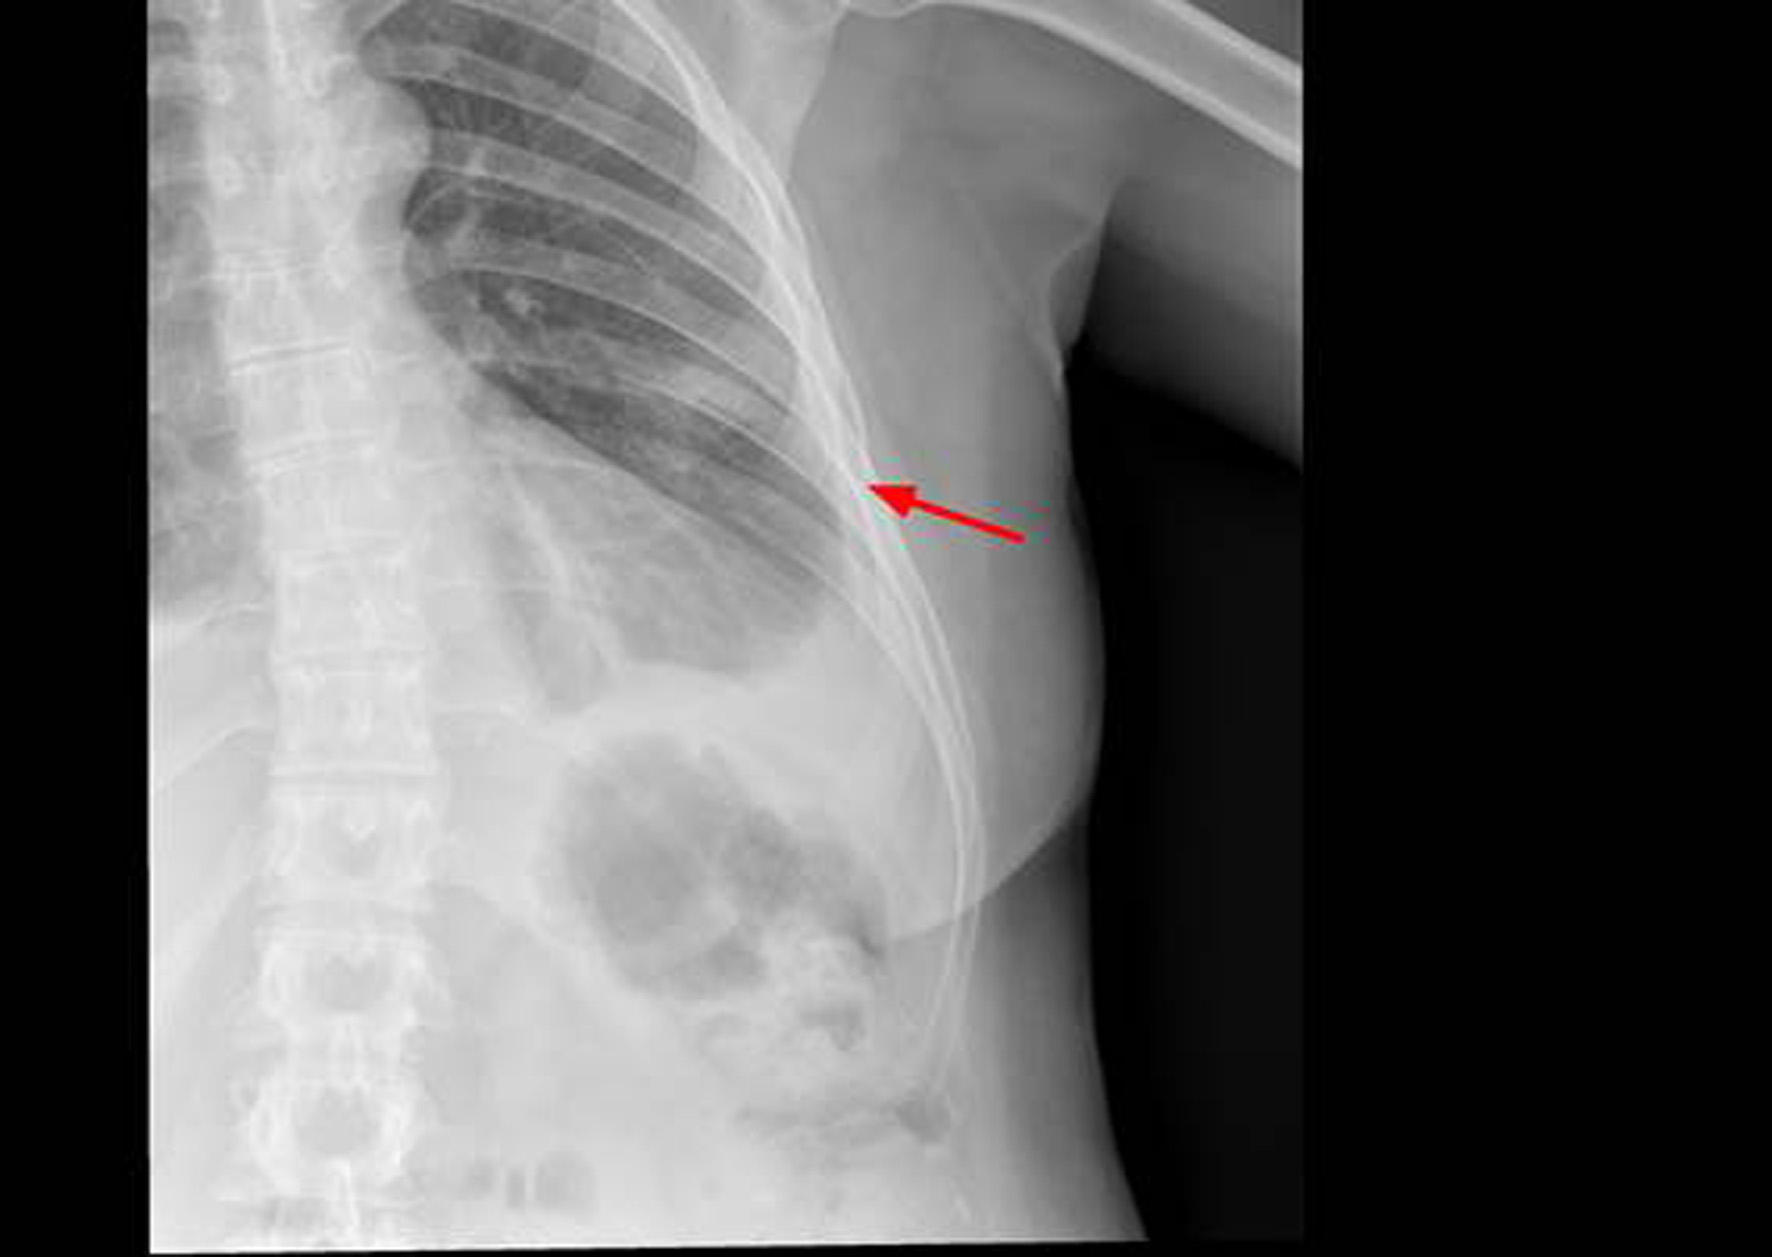

The thoracic X-ray reveals pleural effusion which occupies two thirds of the left hemithorax and the left rib cage. Partial absence of the 6th left costal arch may be appreciated as well (Fig. 1).

Figure 1. X-ray of left rib cage which may show partial disappearance of the 6th left lateral and anterior rib arch.